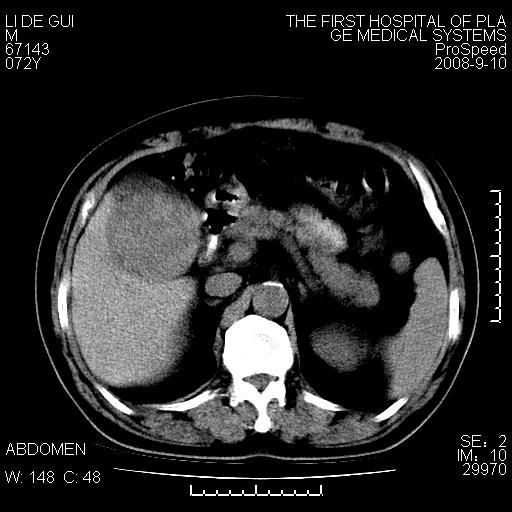

标题: CT17988:腹部肿块两年,肿块大小无变化,患者无不适,自我 [打印本页]

标题: CT17988:腹部肿块两年,肿块大小无变化,患者无不适,自我

胆囊占位性病变(黄色肉芽肿性胆囊炎?)。

考虑-----胆囊血肿机化或胆囊癌或腺肌增生症------增强

胆囊占位性病变,增强。

十二指肠的间质瘤